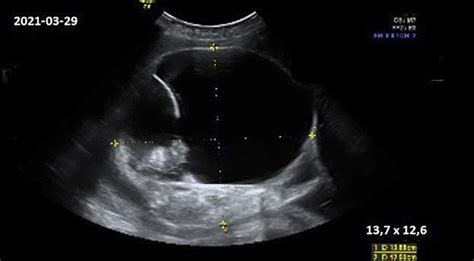

Vaisiaus širdies plakimą galima pastebėti jau ankstyvuoju nėštumo laikotarpiu. Kai CRL (nuo galvos iki uodegikaulio ilgis) viršija 5 mm, 6-ąją nėštumo savaitę, jau matomas širdies plakimas (100-160 k./min.). Matuojant CRL, nėštumo laikas nustatomas 3-5 dienų tikslumu.

Akušerinė echoskopija (ultragarsas)

Akušerinė echoskopija atliekama vaisiaus ir akušerinės patologijos, vaisiaus raidos ydų diagnostikai. Nėra duomenų apie žalingą diagnostinio ultragarso poveikį vaisiui. Jam kontraindikacijų nėra.

Nėščiosioms rekomenduojama atlikti 1-2 ultragarsinius tyrimus, jei nėra papildomų indikacijų. Lietuvoje ultragarsinė nėščiųjų patikra atliekama 18-20 savaitę.